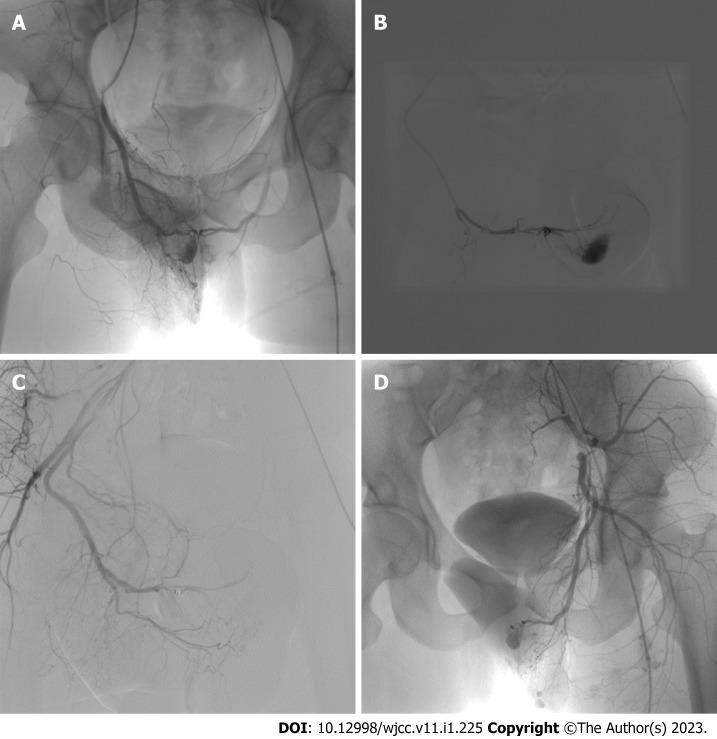

Herein, we report of the case of a 26-year-old Chinese male who presented with a persistent abnormal erection for 12 h after perineal impact injury. Medical history, cavernous arterial blood gas analysis and radiological examinations led to a diagnosis of HFP caused by bilateral cavernous artery fistulas. We performed routine conservative treatment (compression therapy and ice application) for the patient after admission; however, 10 d later, his symptoms had not been relieved. After completion of the preoperative workup, right (severe side) selective perineal artery embolization was performed; the left cavernous artery fistula was left untreated. After postoperative continuation of conservative treatment for 72 h, the patient experienced complete penile thinning. The patient had no symptoms of erectile dysfunction over a follow-up period of 12 mo.

Compared with bilateral cavernous artery fistula embolization, we believe that unilateral cavernous artery fistula embolization can achieve positive clinical efficacy and reduce the risk of postoperative erectile dysfunction secondary to penile ischemia.